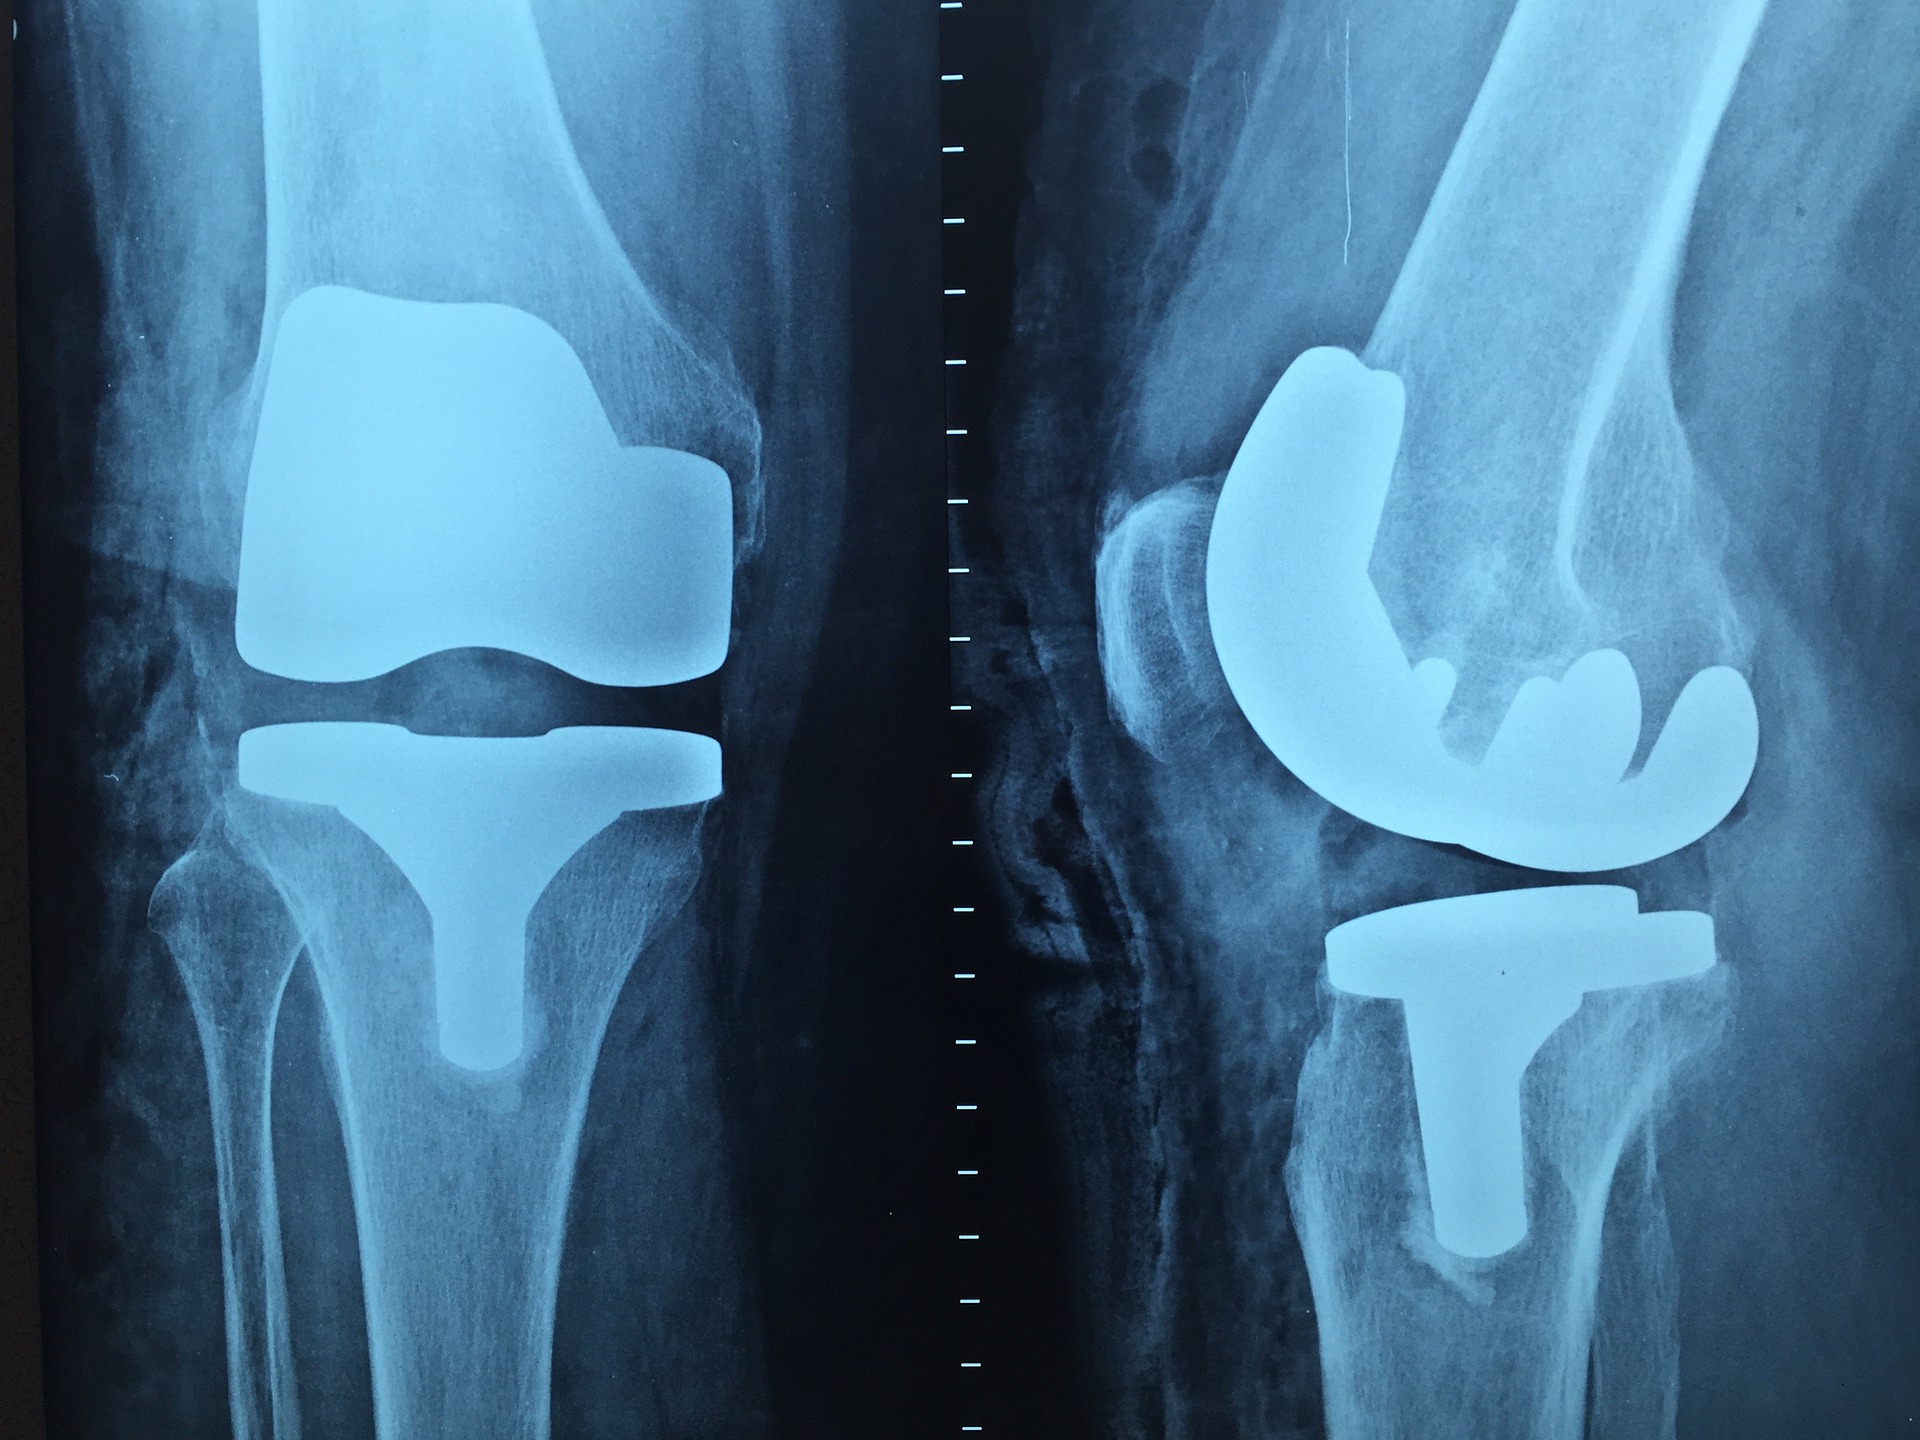

▶무릎통증의 치료

개인마다 무릎통증이 느껴지는 정도가 다르고 증상에 따른 치료방식을 해야 되기 때문에 무릎통증에 대한 검사를 진행한 후 전문의와 상담해야 합니다. 그렇다면 무릎통증을 치료하는 방식은 어떤 것들이 있을까요? 우선 약물치료, 물리치료, 운동치료, 주사치료 등 다양하게 존재를 하며 통증의 정도에 따라 맞는 치료방식을 택하게 됩니다. 약물치료와 주사치료는 말 그대로 약물을 복용하거나 관절에 주사를 놓고 치료를 하는 방식이며 물리치료와 운동치료는 관절을 회복하기 위한 재활치료를 하는데 중점을 두는 치료방식입니다.